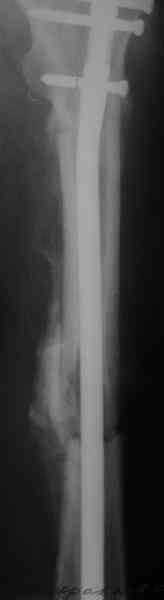

СМ> Если имеются под рукой Р-снимки, продемонстрируйте, плиз.

Вот несколько. С тисками и трубой на днях сделаем.

Моделирование титановых заготовок, в том числе трубой в тисках, при остеосинтезе по Звереву-Ключевскому - тоже широко распространенная

практика, и бедренные гвозди там тоже достаточно мощные...